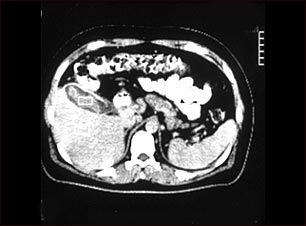

Tomografía computarizada de una colecistitis

TC que muestra colecistitis (cálculos biliares).